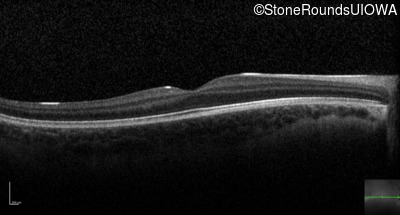

Optical Coherence Tomography - Right - 20/63 -1 sc

Exemplar / OCT Stack

OCT Stack